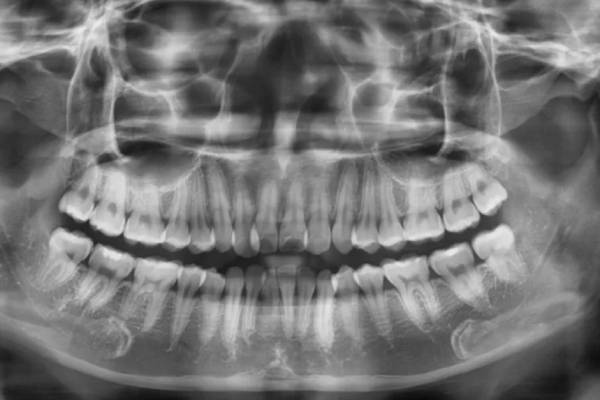

- Chụp X-quang và khám tổng quát tình trạng răng miệng để bác sĩ nắm được chính xác tình hình răng hiện tại.